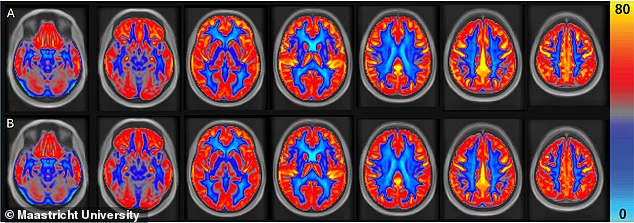

Kết quả chụp MRI cho thấy lưu lượng máu toàn não tăng 3,6% . Lưu lượng máu tại chất xám tăng 4,5%. Hai vùng não liên quan đến trí nhớ và ngôn ngữ cũng có sự thay đổi rõ rệt. Lưu lượng máu tại thùy trán tăng 6,6% và tại thùy thái dương tăng 4,9%.

Thiết kế nghiên cứu cho phép mỗi người tham gia có thể so sánh sự thay đổi của chính mình ở hai điều kiện khác nhau. Các nhà nghiên cứu đánh giá lưu lượng máu não được đo bằng MRI không xâm lấn.

Kết quả cho thấy lưu lượng máu cải thiện ở cả những vùng trọng yếu và trên toàn bộ não. Song song đó, điểm số trí nhớ của những người tham gia cũng tốt hơn khi họ nhớ lại nhiều từ hơn sau 20 phút so với giai đoạn đối chiếu.